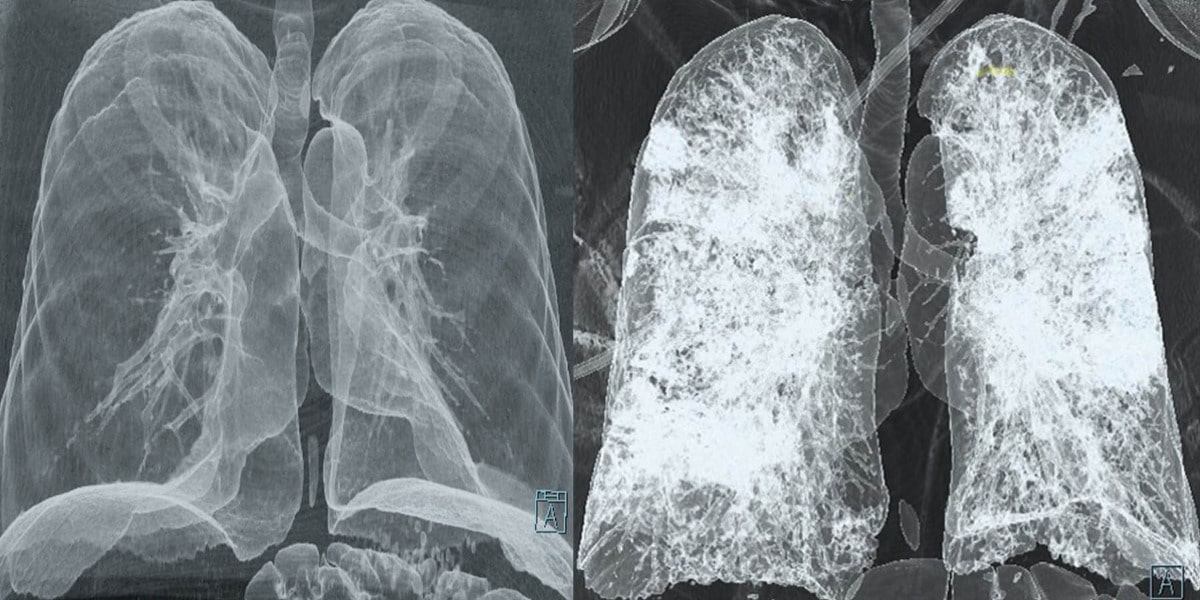

«Все доноры, перенесшие Covid-19, имели определяемые сывороточные IgG к N- и S-белкам, а также RBD вируса вместе с нейтрализующими антителами, в то время как в сыворотке крови доноров органов до пандемии отсутствовали антитела к нему. Используя эту когорту, мы исследовали SARS-CoV-2-специфические Т- и В-клеточные ответы в крови, костном мозге, селезенке, легких», — объяснили авторы статьи.

Как показали результаты, SARS-CoV-2-специфические CD4+ T-, CD8+ Т- и В-клетки главным образом локализовались в легких и связанных с ними лимфатических узлах, а также поддерживались как популяции клеток памяти. Т- и В-клетки памяти, которые участвуют в защите от вторичных вирусных инфекций, тоже наблюдались в основном в легких. «Лимфатические узлы кишечника у некоторых доноров выступали важными участками для SARS-CoV-2-специфических Т- и В-клеток памяти (особенно TRM и BRM). Вероятно, это объясняется тем, что кишечник в некоторых случаях выступает основным местом для репликации вируса», — добавили ученые.

Помимо этого, в ассоциированных с легкими лимфатических узлах выявили SARS-CoV-2-специфические так называемые зародышевые центры B-клеток и TFH-клеток — причем даже у пожилых. Все вместе это говорит о том, что иммунный ответ сохраняется даже через несколько месяцев после выздоровления, а специфическая к SARS-CoV-2 иммунная память локализуется в определенных тканях.